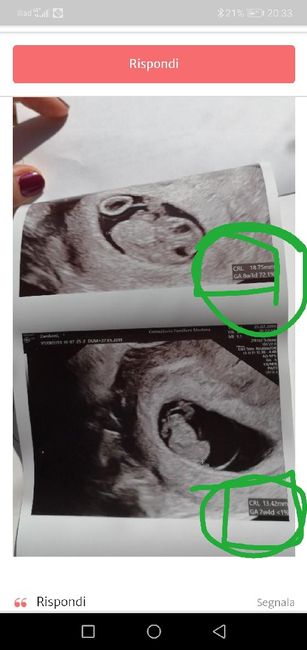

Cara Io so che tu hai scritto 8 + 3 Ma la tua foto che tu hai messo.. Ci sono 2 eco e in una c'è scritto una cosa è nell altra c'è scritto un altra cosa . non so perché...

Maschio o femmina??? 👦🏻 o 👧🏻 3

Comunque quella 8+3 anch'io vedo una femmina... Ti auguro tanto che sia una femmina😊

Ps: per farmi capire perché vedo che non mi hai capito.... Mi sono permessa di fare lo screens hot de la tua eco e evidenziare in basso a dx😉😉😉😉...

Cara allora ti hanno sbagliato a scrivere... perché in una c'è scritto che tu hai 7 settimane qualcosa nell'altra 8 + 3 .... la foto che hai caricato tu😊😊😊

In quella di 7+4avrei detto ♂ invece in quella di 8+3 ♀.... E ma la domanda è....perché 2 eco così ravvicinate? 😂